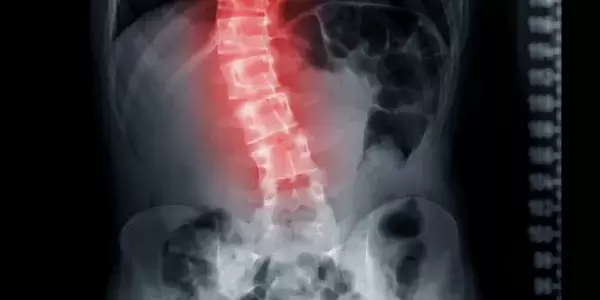

I have severe Scoliosis and have been seeing Rolfers® for over 40 years... At 13, my parents wanted me to wear a back brace, and doctors talked about back surgery. I refused both...